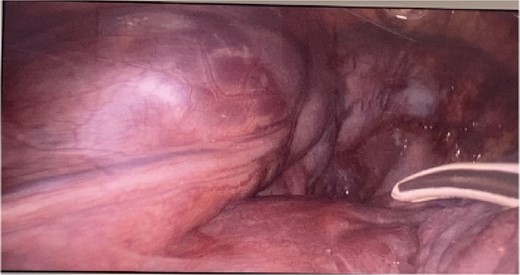

CT imaging, an anterior mediastinal mass was evident (Fig. 2), associated with the presence of thickening of interlobular septa in both lungs (Fig. 3). Surgery is carried out with diagnostic intent with suspicion of lymphoma vs DLP. A mass with cystic characteristics was found, thickening of interlobular septa and lymphatic channels that extended from the lung parenchyma to the mediastinum through the peribronchovascular space, dark serohematic pleural effusion without pleural lesions (Fig. 4).